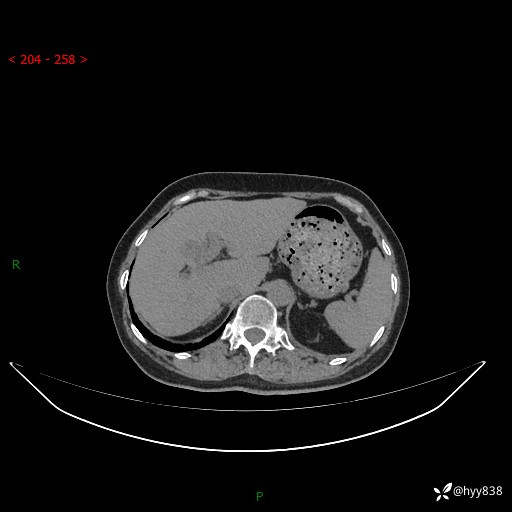

上腹部CT平扫+增强